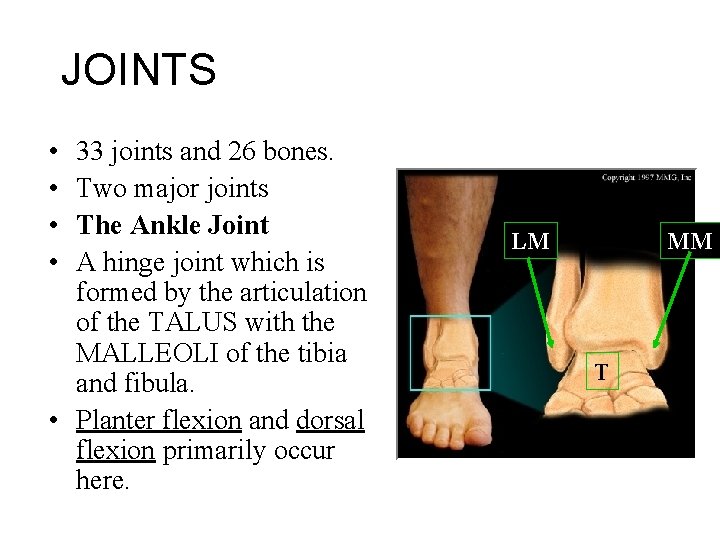

JOINTS • • 33 joints and 26 bones. Two major joints The Ankle Joint A hinge joint which is formed by the articulation of the TALUS with the MALLEOLI of the tibia and fibula. • Planter flexion and dorsal flexion primarily occur here. LM MM T